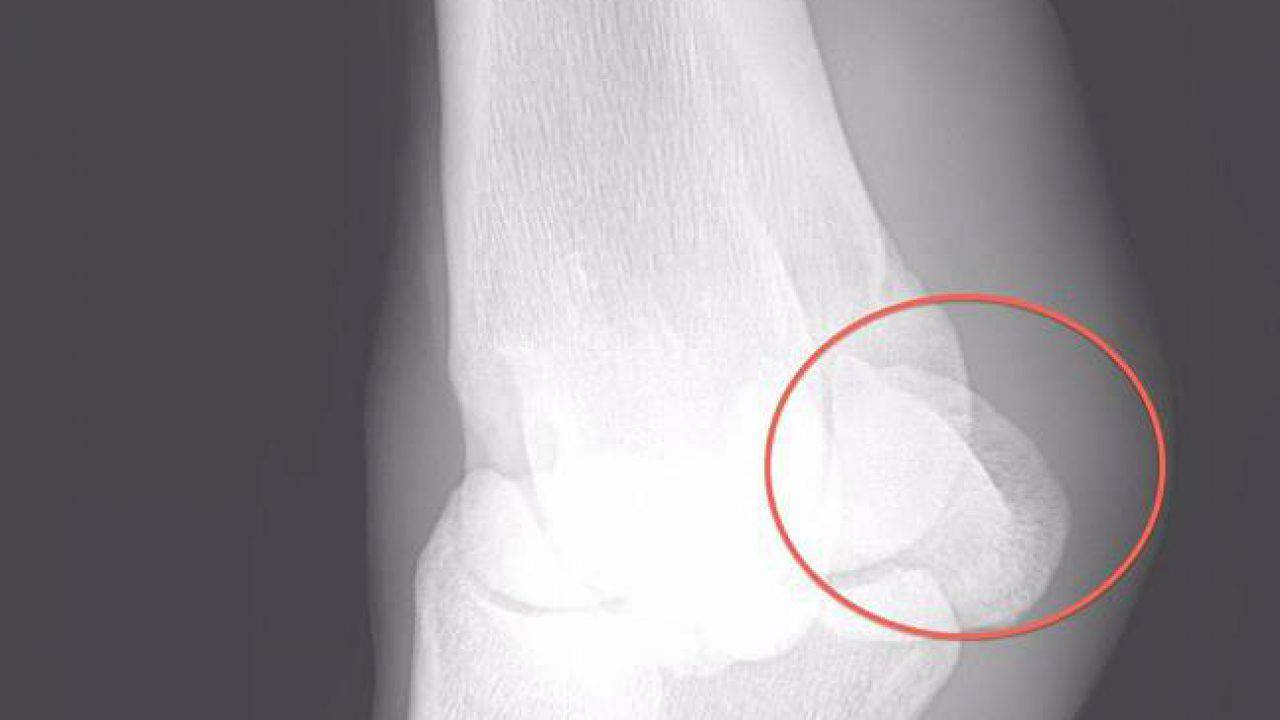

I sesamoidi hanno tipicamente bordi lisci quindi un bordo frastagliato può essere un segno di frattura. La frattura delle ossa sesamoidi dellalluce può. I sintomi principali sono. Maggiori informazioni delle due piccole ossa sferiche alla base dellalluce fratture del sesamoide Fratture delle ossa sesamoidi Le fratture possono verificarsi nelle due piccole ossa sferiche alla base dellalluce sesamoidi. Rigidità dellalluce causata dalla sofferenza della I articolazione tra falange e metatarso.

Il medico potrebbe sottoporsi a raggi X di entrambi i piedi per confrontare la struttura ossea di ciascuno. Vedi anche Panoramica sulle patologie del piede e. In particolare tra tutte le articolazioni e le ossa del piede la prima articolazione metatarso-falangea con il suo complesso sesamoideo è la più comunemente colpita. La sesamoidite è caratterizzata da differenti condizioni di dolore ad insorgenza lenta e graduale sotto la base dellalluce. Pubblicato nel Luglio - Agosto 2015 ne Il Fisioterapista - fascicolo n4.

Le ossa sesamoidi possono fratturarsi praticando la corsa lescursionismo o sport che. Dolore incessante alla base dellalluce. I sesamoidi tibiali e fibulari si trovano allinterno dei tendini del FHB e forma parte della placca plantare. Se si sospetta una sesamoidite o una frattura del piede il medico consiglierà di sottoporsi a una radiografia del piede. Le ossa sesamoidi possono fratturarsi praticando la corsa lescursionismo o sport che comportano atterraggi troppo violenti sullavampiede come il basket e il tennis.